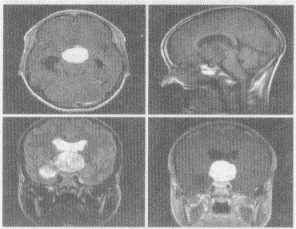

4.男,17歲,視力下降,頭痛嗜睡4個(gè)月,MRI平掃及增強(qiáng)掃描,最可能的診斷為

正確答案:C